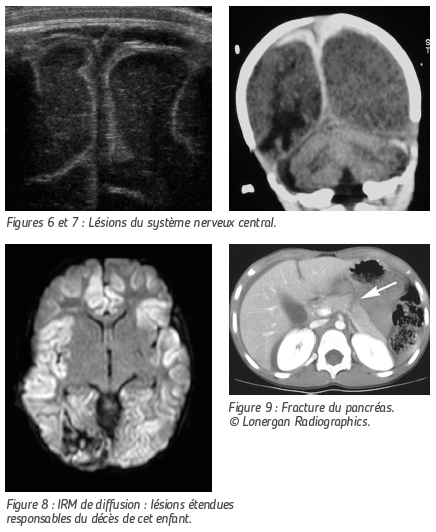

LÉSIONS DU SYSTÈME NERVEUX CENTRAL

Ici encore, le mécanisme lésionnel le plus fréquent chez le nourrisson est le secouage. L’enfant ainsi maltraité peut alors souffrir de graves lésions cérébrales dont les séquelles seront responsables de handicap et qui peuvent entraîner la mort de l’enfant.

L’échographie transfontanellaire n’est pas formellement indiquée mais dans certaines circonstances, elle permet de mettre en évidence fortuitement et de façon non irradiante les lésions hémorragiques interhémisphériques « biphasiques » typiques.

Le CT Scanner est d’accès facile et permettra lui aussi de mettre en évidence les zones de contusion, les hématomes et les ruptures des « veines ponts ».

L’IRM est indispensable pour le bilan lésionnel complet. Cet examen n’est pas pratiqué en urgence car il nécessite une anesthésie générale chez le petit enfant.

Les séquences adaptées permettent d’évaluer l’étendue des lésions anoxo-ischémiques dont le pronostic peut être très sombre en matière de séquelles, voire de survie de l’enfant.

LÉSIONS VISCÉRALES

L’enfant maltraité peut être aussi victime de lésions viscérales : fracture du pancréas, du foie ou de la rate. L’échographie et le scanner permettent d’en faire le diagnostic.